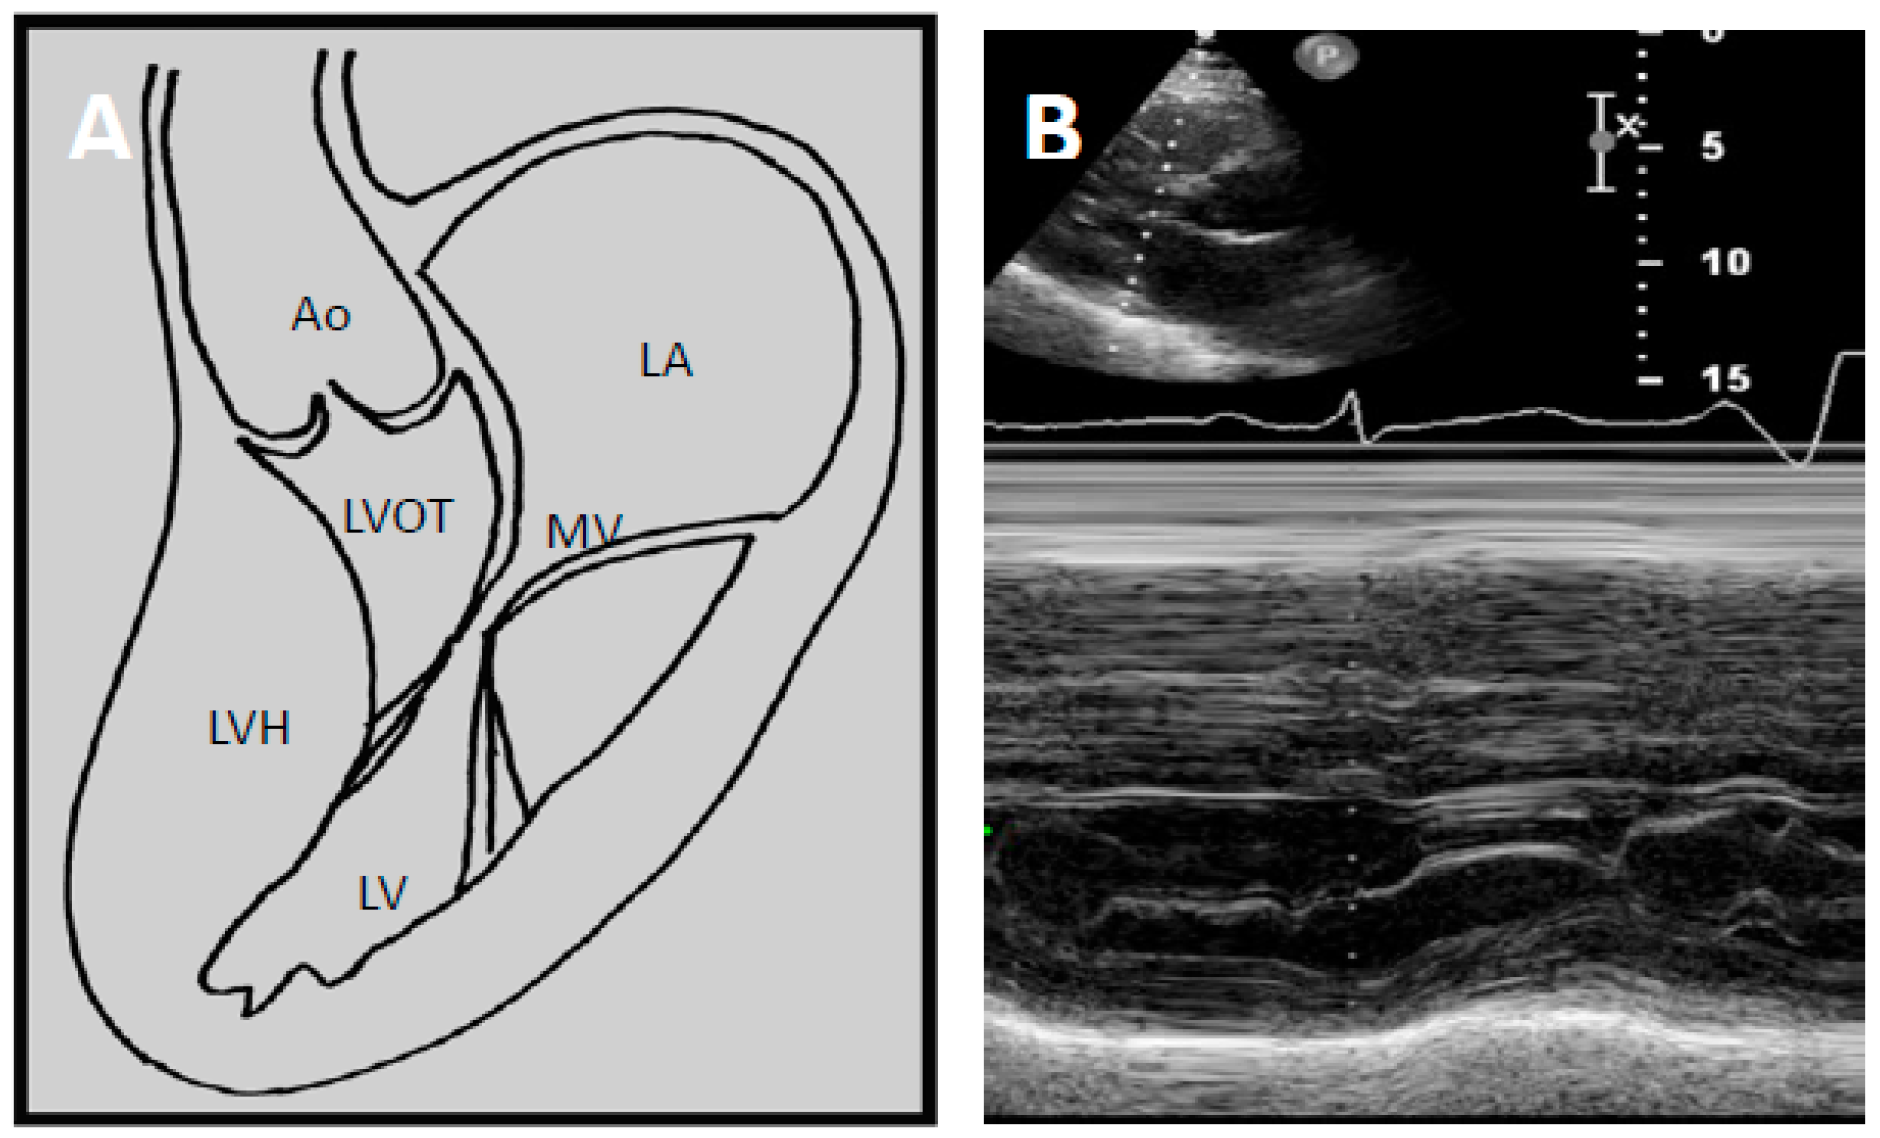

4.2. Echocardiography

5. Current Diagnostic Techniques